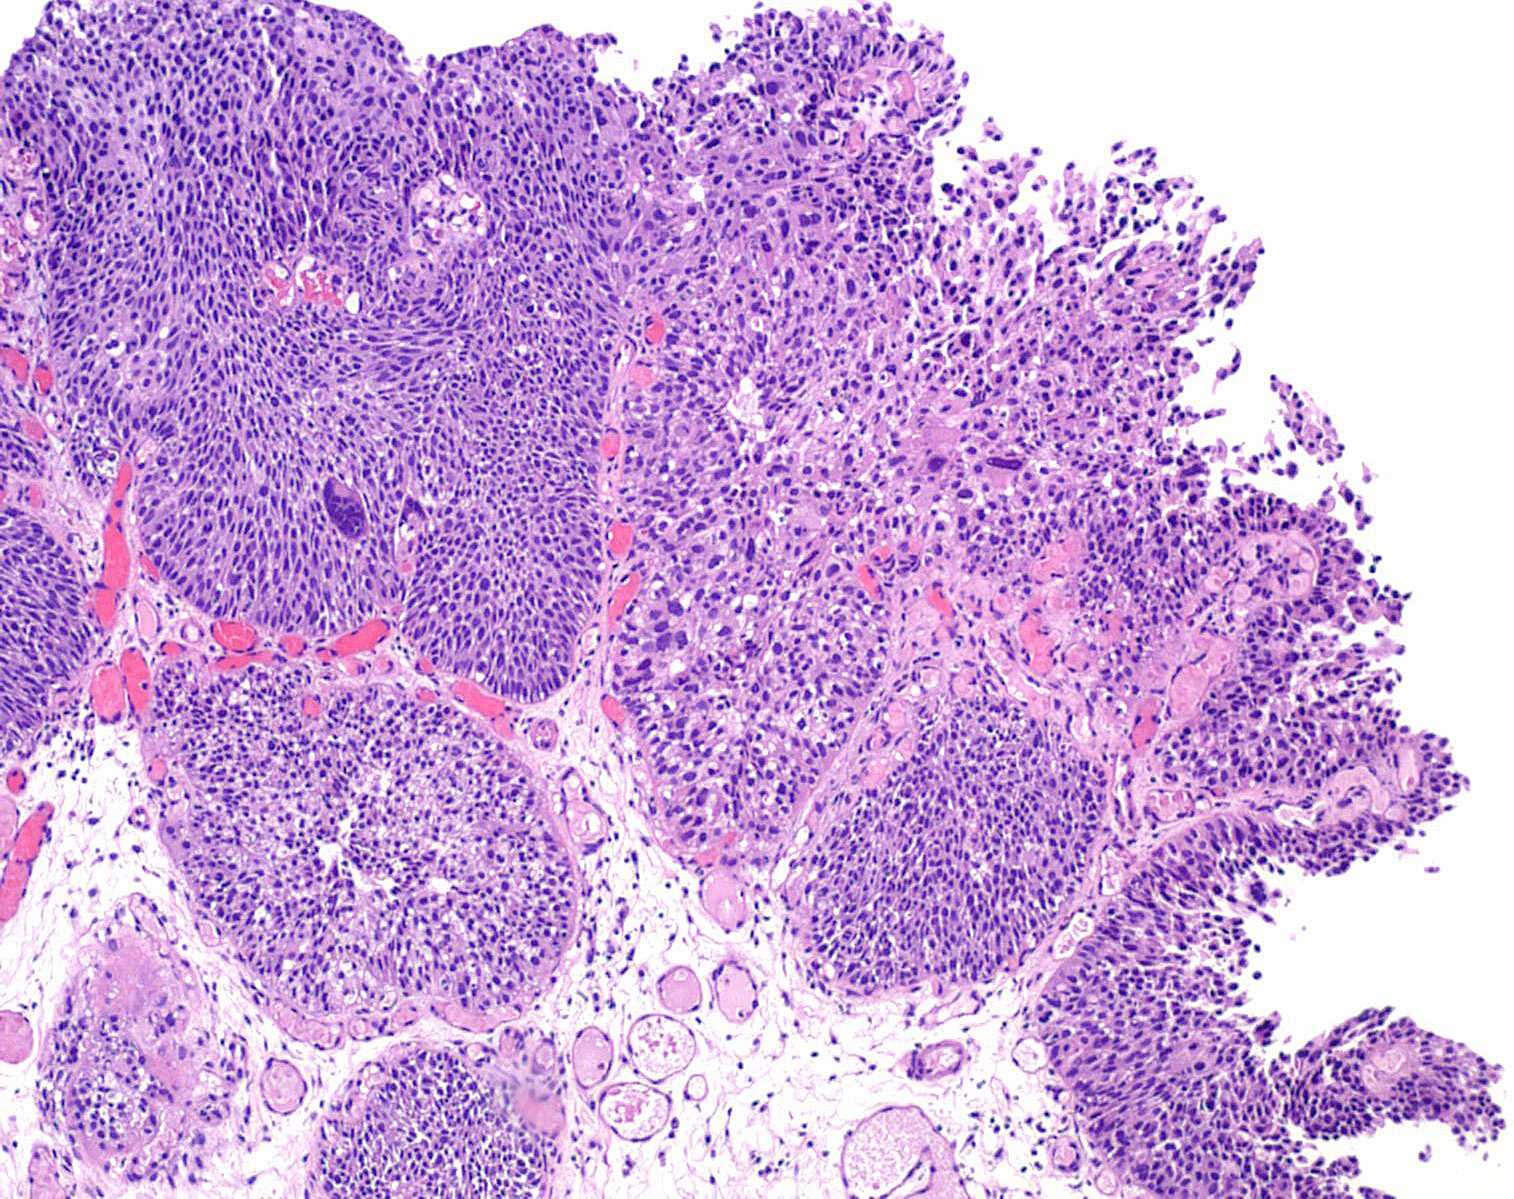

Bladder Papillary Lesions

Case ID: 193